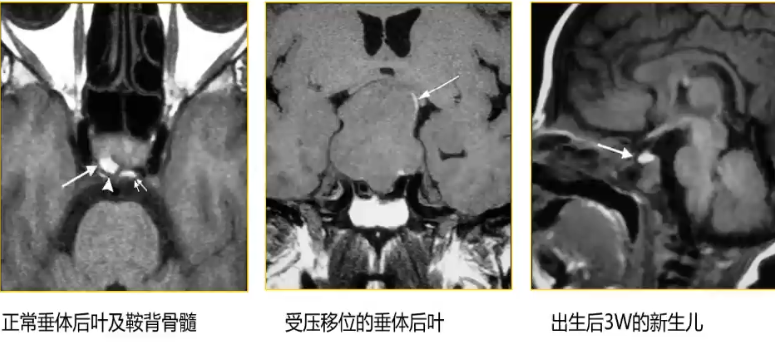

1. 正常表现:神经垂体含抗利尿激素分泌颗粒;蝶鞍区正常或变异

骨髓;垂体前叶活跃的激素分泌(新生儿、孕妇及哺乳妇女)